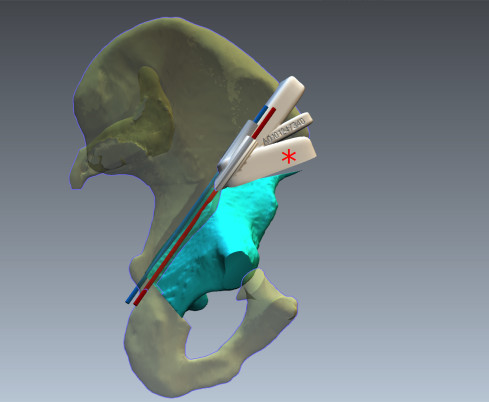

3D-tiskalniki omogočajo tiskanje želenega dela skeleta iz CT-slik. To možnost so sprva izkoriščali travmatologi predvsem v primerih kompleksnih zlomov medenice. Kirurg lahko na modelu preveri, s kakšno situacijo se bo soočil med posegom, poskusi problem razrešiti na različne načine in izbere najbolj primerno rešitev za pacienta. Nova tehnologija omogoča tiskanje kirurških orodij iz različnih materialov. V rekonstrukcijski ortopediji so se uveljavili printani nosilci z utori, ki jih med posegom lahko uporabimo za natančno izvedbo osteotomije in kirurške učvrstitve zloma (osteosinteze) (slika 5).

Slika 5. Računalniški prikaz uporabe 3D printanega nosilca (označen z živo rdečo zvezdico *) za natančno izvedbo vertikalne osteotomije črevnične kosti